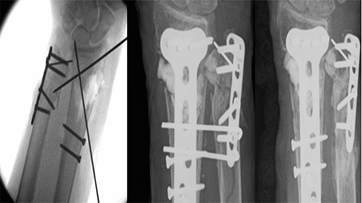

Examples of applications of bone grafts are illustrated in Figures 1-3.

Figure 1: Metaphyseal comminution with a large segment of bone loss.

K wires did not adequately hold the temporary reduction of the fracture. A synthetic bone graft was used to fill the bone void and maintain the stability of reduction for fixation. (Lt: intra-op fluoro showing metaphyseal defect; Middle: immediate post-op; Rt: four months).

Figure 2: Large metaphyseal defect bridged with a corticocancellous autologous iliac crest graft shows union at 3-months.

Lt to Rt: intra-op fluoro showing metaphyseal defect, immediate post-op, AP + Lat at three months.

Figure 3: Metaphyseal bicortical defect with fracture shortening.

Bone graft in the form of a bone block was used to restore the radial height and stabilization of the fracture reduction before the application of the locking plate.